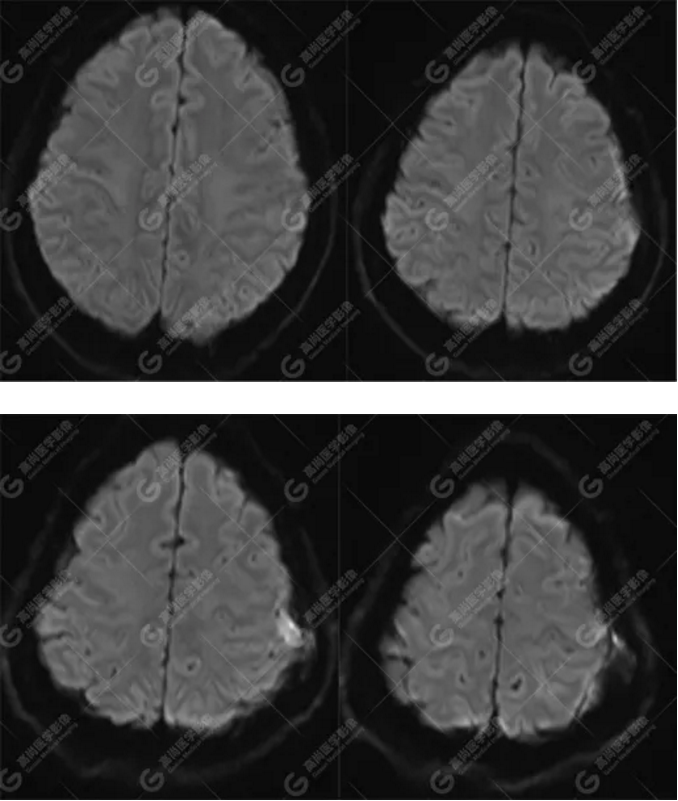

MR圖像

左側(cè)額頂部顱骨骨質(zhì)破壞并相鄰硬腦膜增厚強(qiáng)化,考慮Rosai Dorfman?。≧DD)可能,需與朗格漢斯細(xì)胞組織細(xì)胞增生癥鑒別。

典型的RDD在MRI上T1WI 呈等信號(hào),T2WI及 DWI為等-低信號(hào),增強(qiáng)掃描多為明顯均勻強(qiáng)化,多伴有腦膜尾征,部分病例伴有不同程度的腦水腫。T2WI 像 RDD 病灶中出現(xiàn)聚集的低信號(hào)影及 CT檢查沒有鈣化是 RDD 的特征性影像學(xué)表現(xiàn)。

總之,顱內(nèi)RDD是一種罕見的硬腦膜良性病變,若 MRI發(fā)現(xiàn)顱內(nèi)基于硬腦膜扁平或匍匐生長(zhǎng)的孤立或者多發(fā)腫塊,CT 檢查未見鈣化,而MR檢查T2WI及 DWI呈低信號(hào),增強(qiáng)明顯均勻強(qiáng)化,應(yīng)考慮到 RDD 的可能。